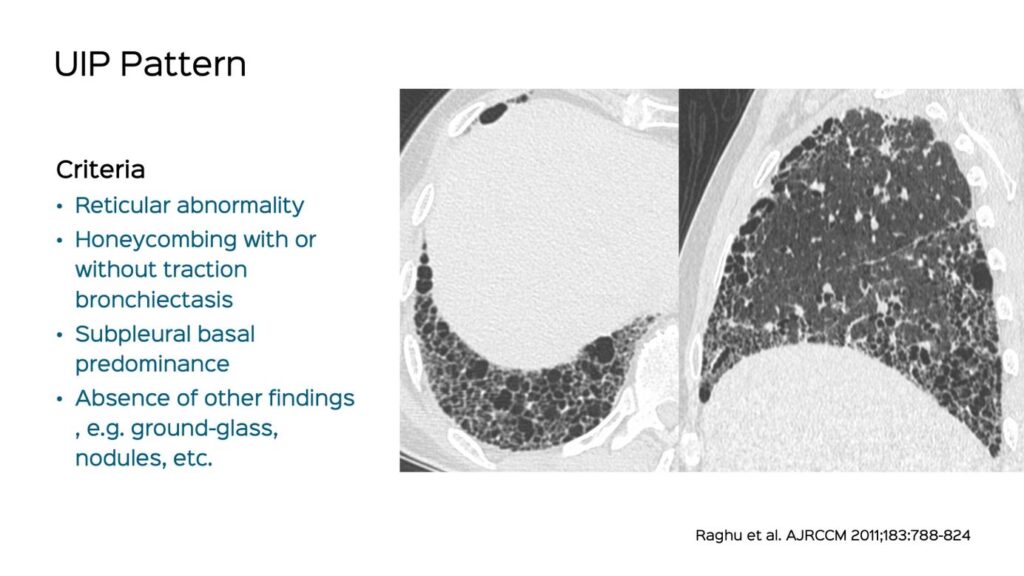

- Udvikling af Fibrose: Over tid fører den konstante aflejring af arvæv til en omstrukturering af lungearkitekturen. Dette resulterer i dannelsen af såkaldte "bikage-cyster" (honeycombing), som er et klassisk tegn på avanceret UIP og kan ses på en HRCT-scanning.

- Billeddiagnostik: Højopløselig computertomografi (HRCT) er det vigtigste værktøj til at diagnosticere UIP. Et typisk UIP-mønster på HRCT viser retikulære (netlignende) fortætninger og bikage-cyster, primært i de nedre og ydre dele af lungerne.